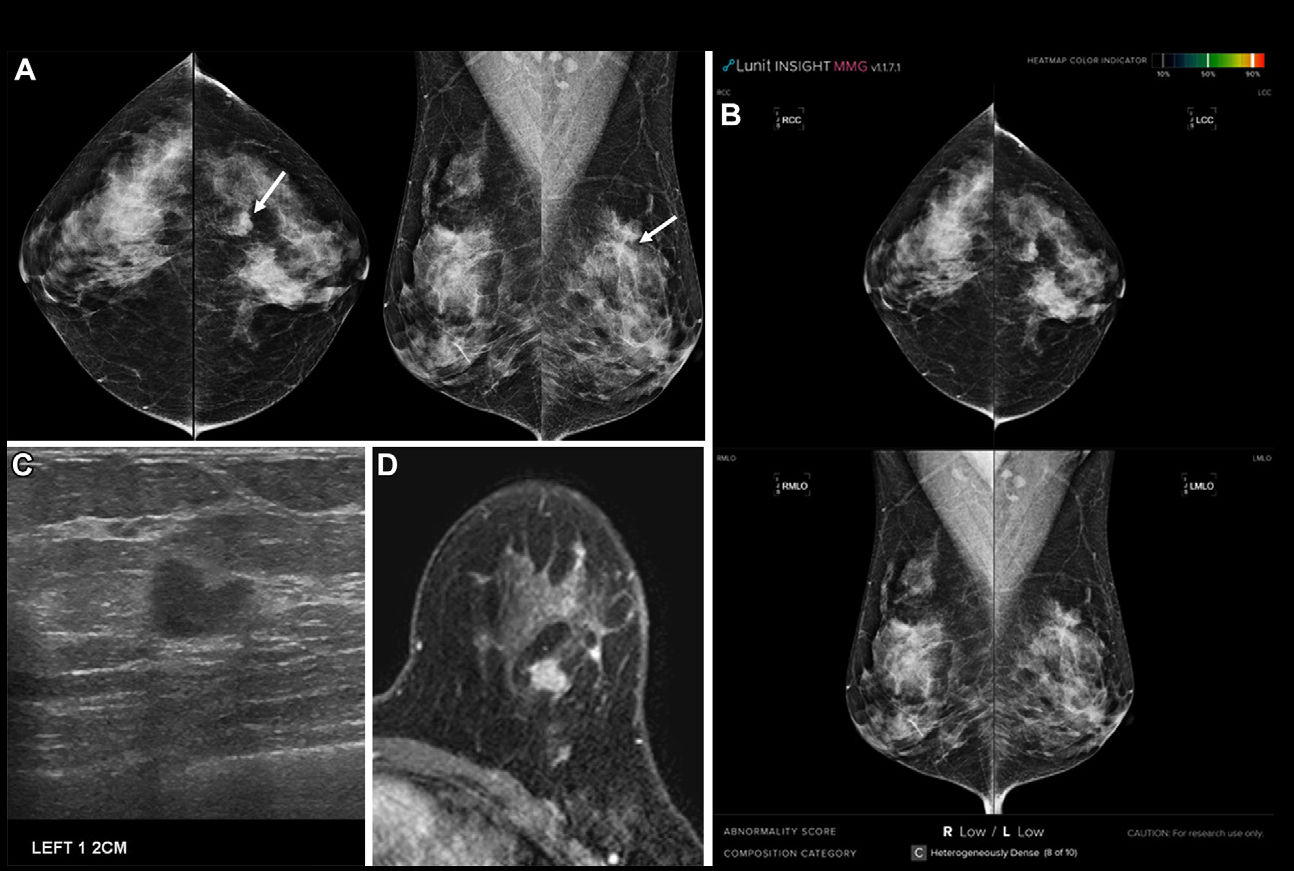

Researchers led by Shu Jiang, PhD, from Washington University in St. Louis, MO, reported that their AI model, which generated mammogram risk scores from both current and prior mammograms, performed well across diverse racial and ethnic populations in a province-wide screening program starting at age 40.

Jiang and colleagues tested the performance of their dynamic risk prediction model incorporating prior mammograms, which was previously validated in Black and white women. They tested the model in a province-wide screening program in British Columbia, where mammographic breast screening starts at age 40 years and is provided every other year.

Using up to four years of prior mammograms in addition to the most current mammograms, the model achieved an area under the receiver operating curve (AUROC) of 0.78 based on analyzing images alone. It also achieved consistent results throughout the study’s subpopulations. This included the following AUROC values: 0.77 in East Asian women, 0.77 for Indigenous women, and 0.75 for South Asian women.